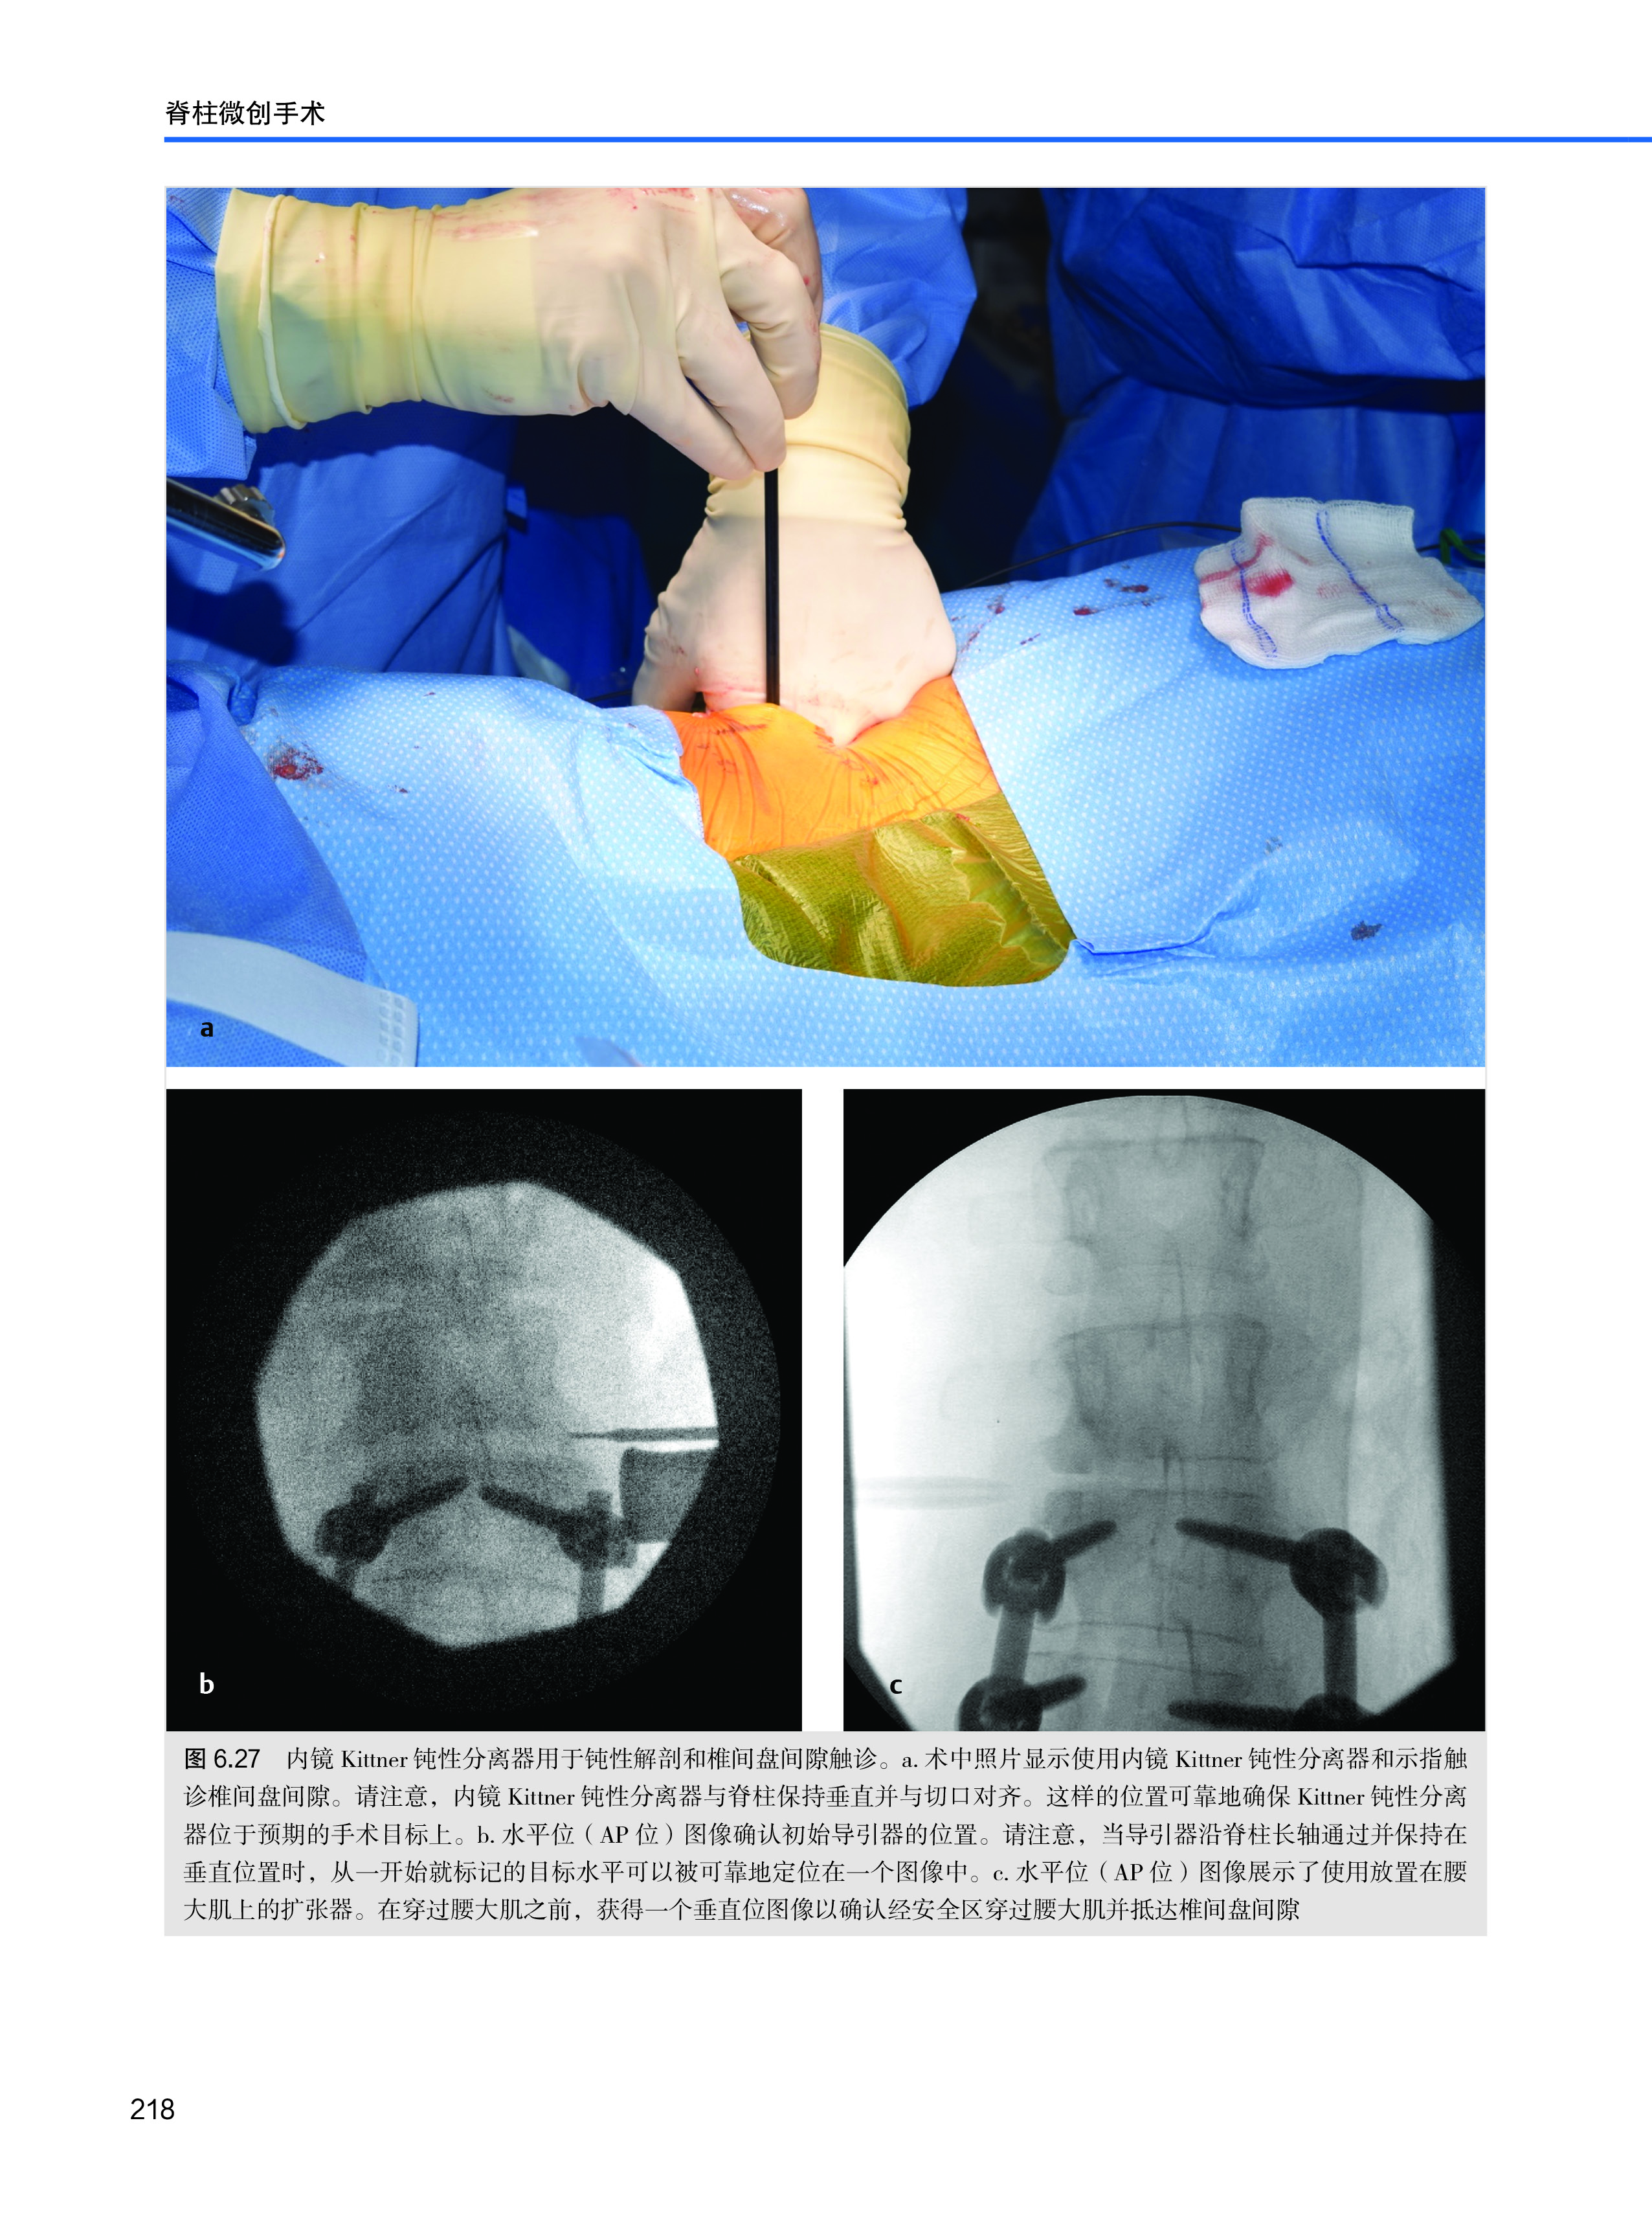

这本入门读物是一本全面的、详细的关于包括颈椎、胸椎和腰椎在内的脊柱微创手术的图书。它用详细的 3D 插图、图示和诊断性研究对脊柱微创手术进行了极好的说明。在这本书中,Tumialán 博士不仅详细介绍了脊柱微创手术的手术技术和细微差别,同时还描述了这些技术演变成他常规使用的微创手术的过程和历史背景。在每一章中,他强调手术干预的依据以及使用微创技术的优势,并对手术解剖进行了细致、精美的说明。在这本书中,他强调了脊柱在每个节段上的独特解剖。对读者来说,幸运的是,Tumialán 博士运用他在脊柱微创手术方面的丰富经验,像协助手术一样指导读者理解每项技术。